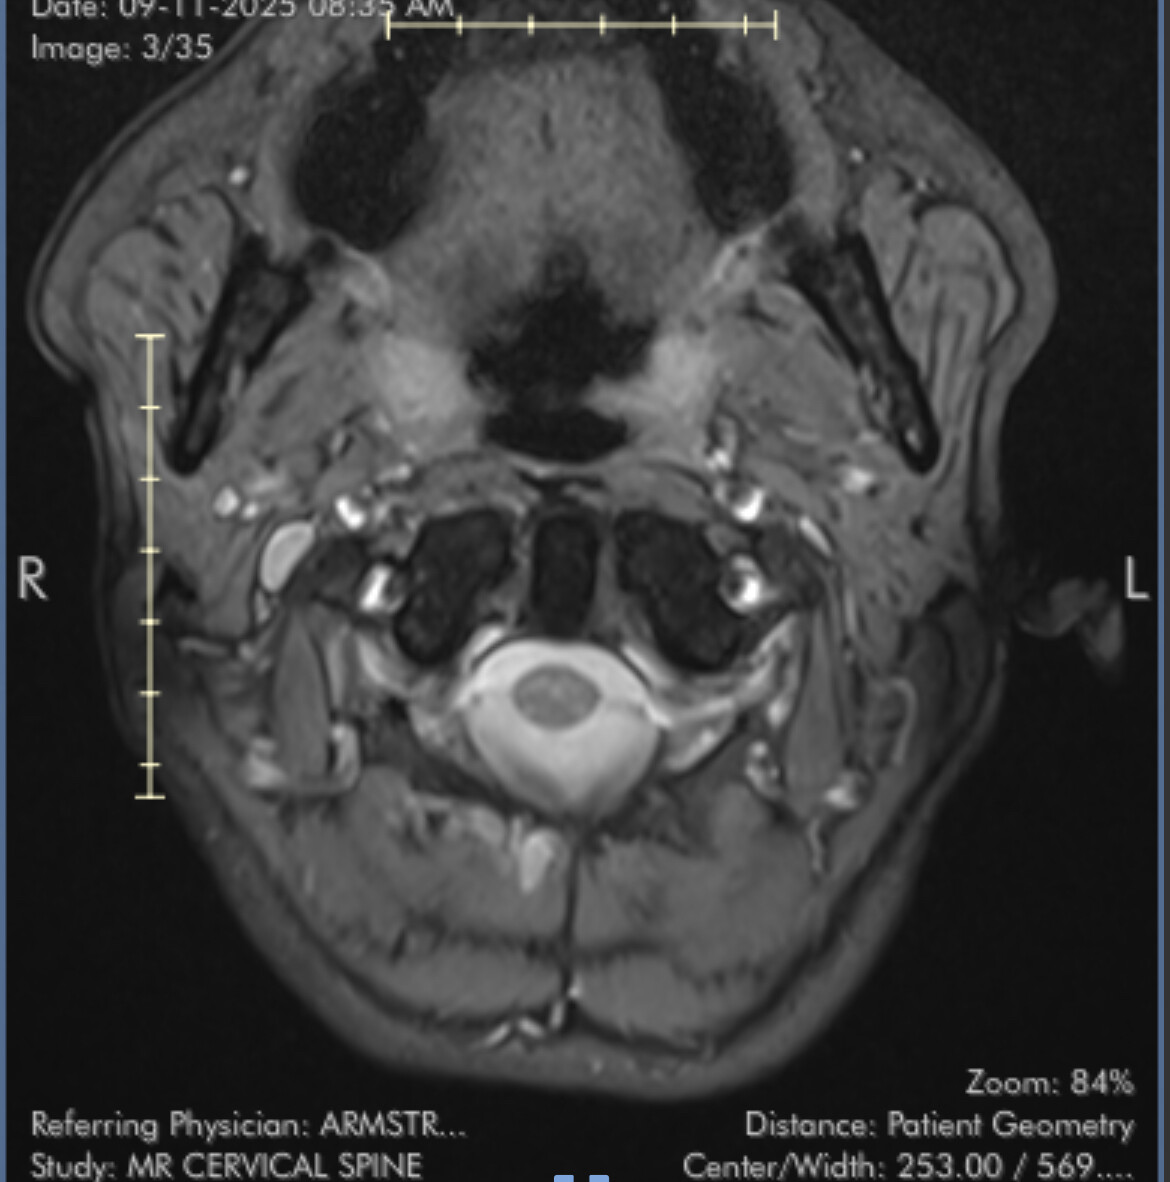

First stage of diagnosis - MRI images

I’ve uploaded some images now. I know they aren’t ideal but I’ll hopefully get my hands on the CT angiogram I had at A&E soon.

I marked the images for you and marked the IJV.

So you can see how the IJV passes by the transverse processes of C1 which are compressing. In this position the right IJV does not have severe compression, but in Figure 2 you can see that the left IJV is almost invisible, and in the other images there is significant narrowing.

On MRI, it is very difficult to see the styloid processes.